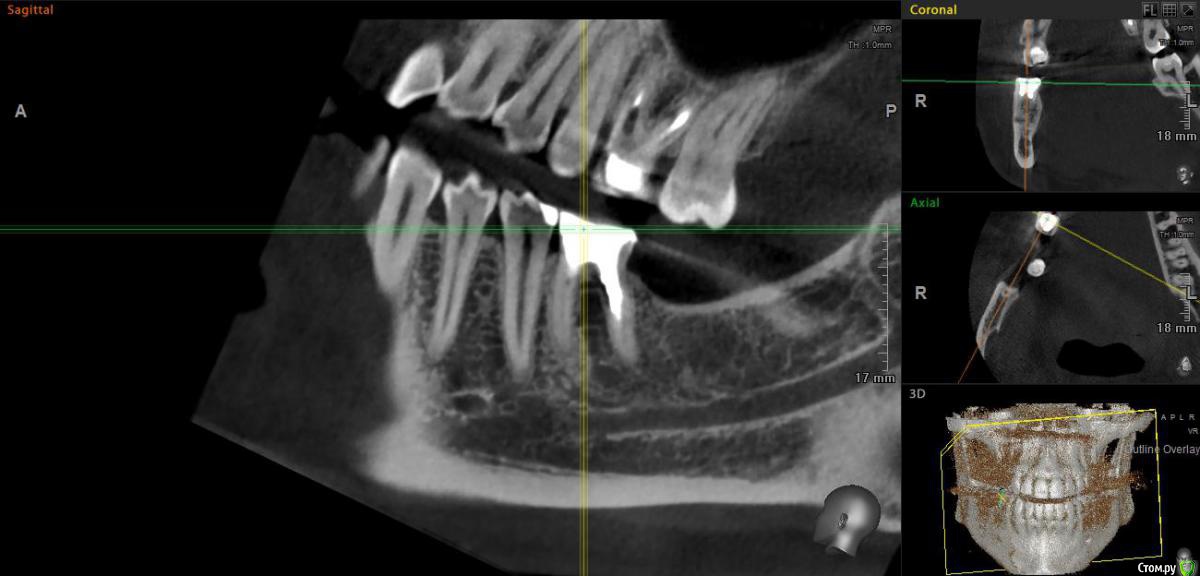

bbss Опубликовано 6 июля, 2018 Автор Поделиться Опубликовано 6 июля, 2018 Здравствуйте.Скажите пожалуйста, можно ли что-то сказать по-моему снимку о 6 снизу и 6 сверху? Ссылка на комментарий